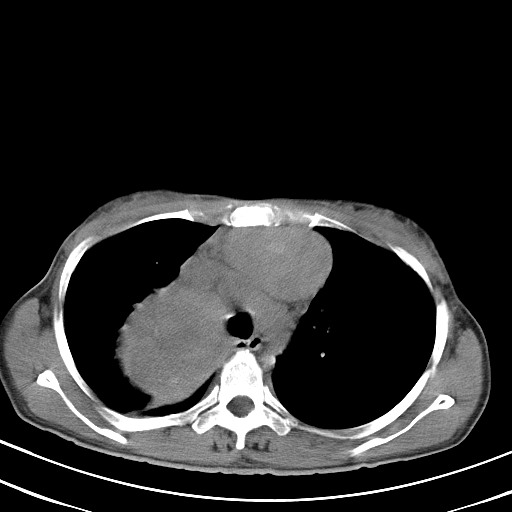

以下是引用汪涛同志在2007-8-2 0:40:00的发言:[br]病变虽然广泛,同时侵及双侧纵隔,但是无论左侧和右侧上下观察都是与右侧颈部甲状腺相延续的,而且强化幅度基本一致,又同时具有恶性病变病变的某些特征:肿块过大且密度不均,部分层面与正常纵隔结构分界不清,结合病史已有两年,考虑:胸内甲状腺肿恶变可能。[br]